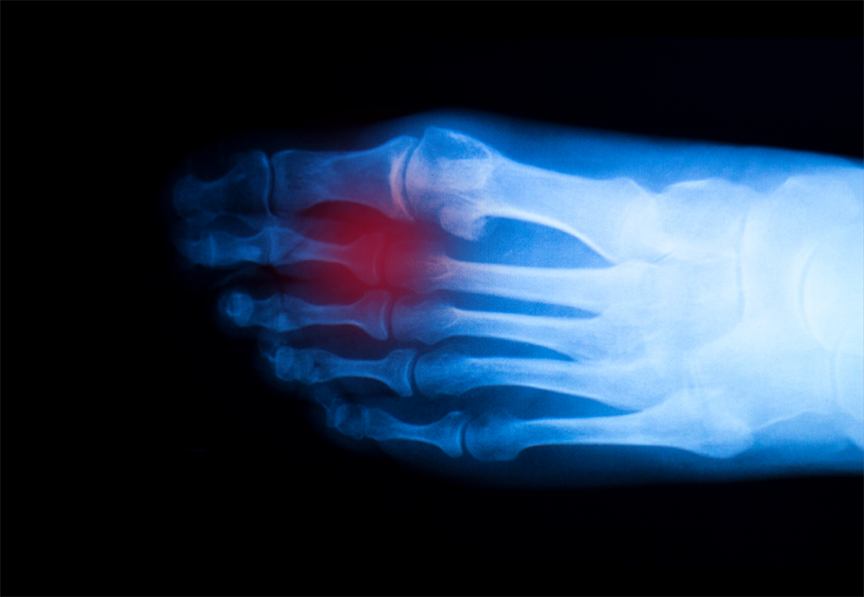

Recently a news report was released by the Washington Post that was titled A Pandemic of Broken Toes.” This was taken from a quote by an orthopedic surgeon named John Keeling, who has seen an influx - an estimated tripling or quadrupling - of broken toe cases during quarantine. While a broken toe isnt a serious medical condition, it can be painful and require medical treatment.

So why have there been so many broken toe cases in quarantine? According to the experts interviewed in the above report, its because were spending more time at home without shoes on, our feet unprotected. This risk is particularly heightened due to the fact that were also now exercising at home too.

That being said, if you drop something heavy on your toe or stub the toe bumping into something, you may experience a searing pain, which may be reflective of a fracture. Some other symptoms include:

• Swelling

• Stiffness

• Bruising

• Difficulty walking

These symptoms may vary in intensity, but if you have experienced trauma to the toe and it continues to hurt past the point of immediate recovery, you may have broken it and require medical attention. If a broken toe isnt given sufficient medical attention, it may not heal completely or improperly, causing long term complications like deformity, arthritis, and reduced mobility or range of motion, potentially requiring surgery or continual medical treatment.